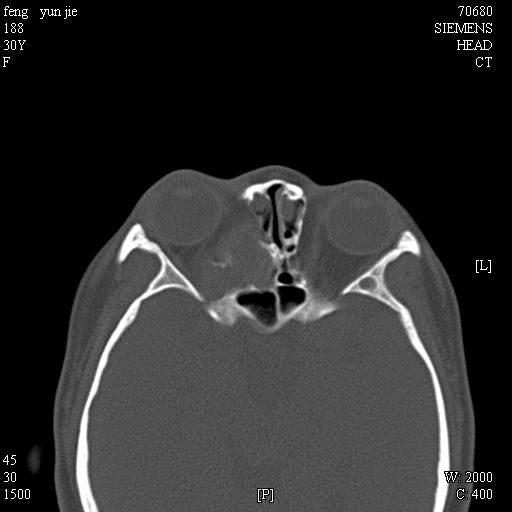

女,37岁,多年前鼻骨骨折过,现在穿刺有炎性分泌物

考虑:1、鼻骨陈旧性骨折;

2、额窦粘液囊肿(右侧水平额窦突入眶内上方)可能性大。

1)左侧鼻骨骨折(陈旧性)。2)双侧额窦及双侧筛窦炎症,伴右侧额筛窦黏液囊肿突入右侧眼眶。